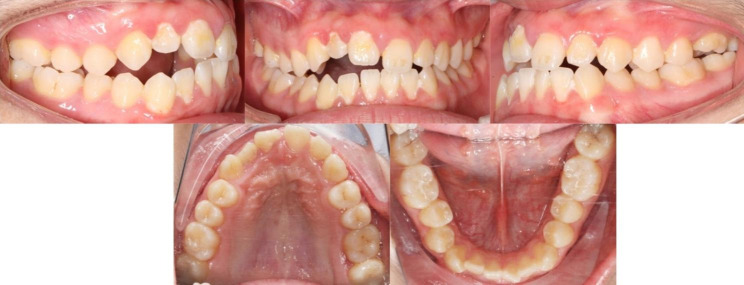

The clinical examination revealed that the right maxillary anterior teeth of the proband [11–13] were below the occlusion plane, forming an open-bite of 4 mm. The eruption height of the left maxillary first molar (26) was slightly insufficient. Bilateral molars were of a complete mesial relationship (Fig. 1). All the impacted teeth had no caries or enamel defects, and the position of the adjacent teeth was normal. There were no other apparent physical abnormalities in all four quadrants.

Fig. 1.

Pretreatment intraoral photographs